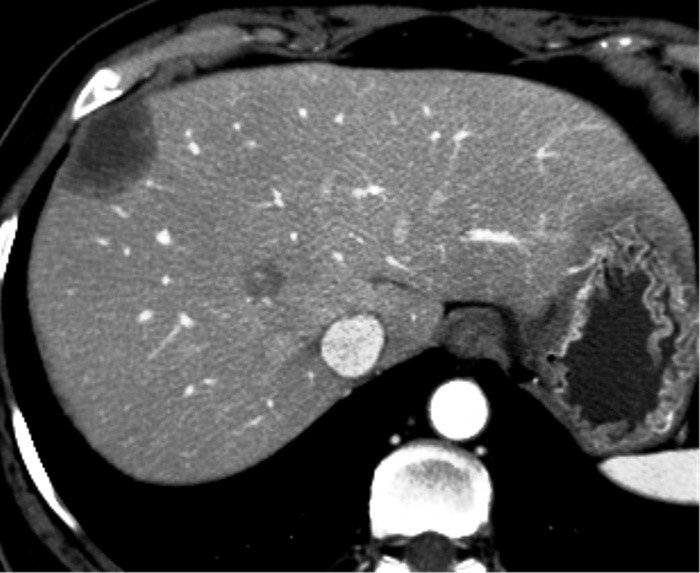

• NET-in qaraciyər metastazlarının xarakterik xüsusiyyəti hipervaskulyar olmasıdır ki, bu da Doppler müayinəsində intensiv axın şəklində, kontrastlı müayinələrdə isə arterial fazada kontrastlaşma və venoz fazada yuyulma əlaməti ilə təyin edilir.

• Hipervaskulyar törəmələr